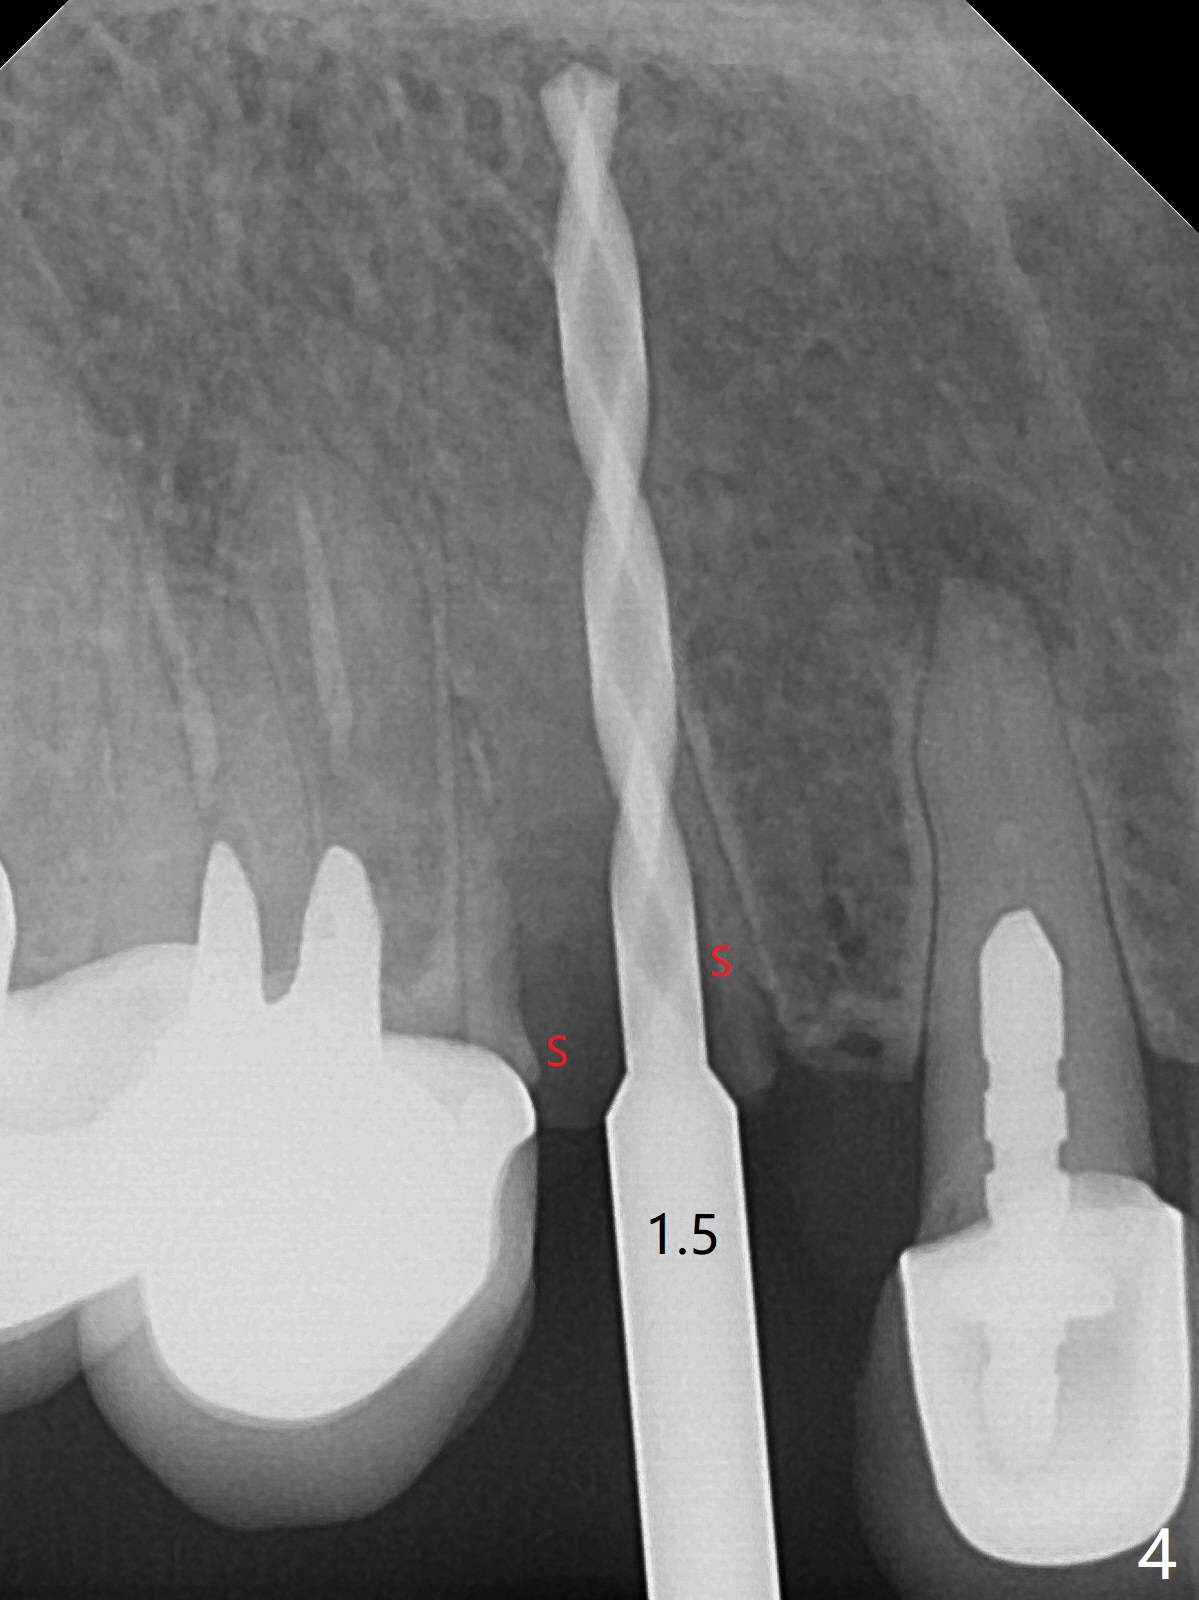

防止拔牙后颊侧骨板萎缩最有效方法是保留部分牙根,例如颊侧(外形象盾牌,简称盾,socket shield (S)),但是制备特别麻烦,尤其是上尖牙。60岁女右上3颊侧骨板隆起(图一至三:*),但是相当狭窄(上下方向),预计强行拔除,势必损失颊侧骨板,造成颊侧塌陷,准备保留盾,如图三红虚线,图六(术后3D长轴断面(十字架:植体))S代表。其实术中试图将整个牙根一起拔除,但是仿佛不行,只好静下心来分根,制备盾,不过困难重重,尤其是除去根尖(防止残余感染),最长外科裂钻似乎达不到根尖,取出后者,颊侧根尖骨板穿孔(图七:箭头)。然后腭侧钻洞(图四),当最后一个钻头保持原位时,在颊侧根尖穿孔处植入粘性骨粉(从牙槽窝口进入,原本粘性骨粉为了修复大面积颊侧缺损用(万一需要强行拔除)),然后才把一段式植体植入(图五),在其余空间填入骨粉,稍微制备基台,制作临时牙冠,最后在牙槽窝开口塞入PRF膜,衬里牙冠,不暂时取出牙冠,衬里相当于临时粘固剂。术后一个月牙根片段和临时牙冠维持良好的牙龈外形(图八,九);术后两个月病人嫌尖牙龈端太尖太长,临时牙冠龈端调整(图十,十一),但愿一个月后龈缘合乎病人期望。